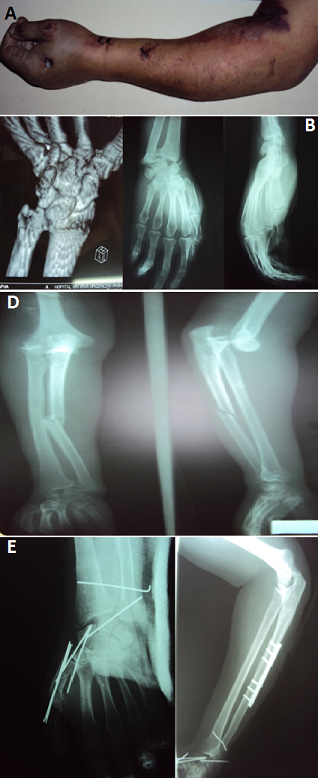

Les luxations concomitantes ipsilatérales du coude et du poignet (floatingforearm) constituent une lésion très rare. Les luxations périlunaires surviennent suite à un traumatisme à haute énergie par hyperextension. Le diagnostic nécessite souvent le recours au scanner du poignet. Selon la force exercée sur le poignet, d'autres lésions peuvent y être associées. Le traitement est urgent et consiste en une réduction et stabilisation des articulations atteintes, suivi par un programme adapté de rééducation fonctionnelle du membre traumatisé. Nous rapportons l'observation d'un patient âgé de 56 ans, commerçant, droitier, tabagique chronique. Victime d'un accident de circulation avec traumatisme du membre supérieur gauche. L'examen clinique trouvait un avant-bras et main gauches œdématiés, coude et poignet déformés et ecchymotiques (A). L'examen vasculo-nerveux était normal. Les radiographies de l'avant-bras, du coude, du poignet et de la main gauches face et profil avec scanner du poignet,avaient objectivé des luxations postéro-externe du coude gauche, périlunaire antérieure du carpe et de la radio-ulnaire distale avec fracture diaphysaire de l'ulna, fracture de la styloïde radiale, fracture du scaphoïde carpien trans-tubérositaire type IV de Schernberget fracture de la base du 1er métacarpien (B,C). Le traitement avait consisté en une réduction orthopédique de la luxation du coude, ostéosynthèse de l'ulna par plaque spécial radius, double embrochage du scaphoïde, réduction et stabilisation de la luxation périlunaire et de la radio-ulnaire distale et embrochage de la base du 1er métacarpien (D).